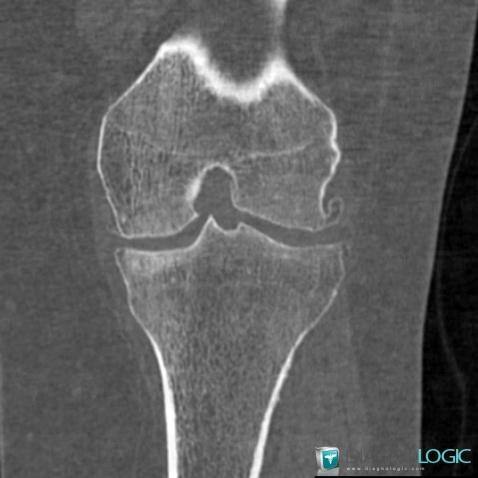

Ostéochondromatose synoviale, Articulations fémoro tibiales / Echancrure, Scanner

Voici les informations spécifiques à l'image clé ci dessus:

- Diagnostic Ostéochondromatose synoviale, Localisation(s) Articulations fémoro tibiales / Echancrure, comportant les gammes Calcification intra ou périarticulaire, Masse des parties molles juxta articulaires, Arthropathie avec nodules des parties molles